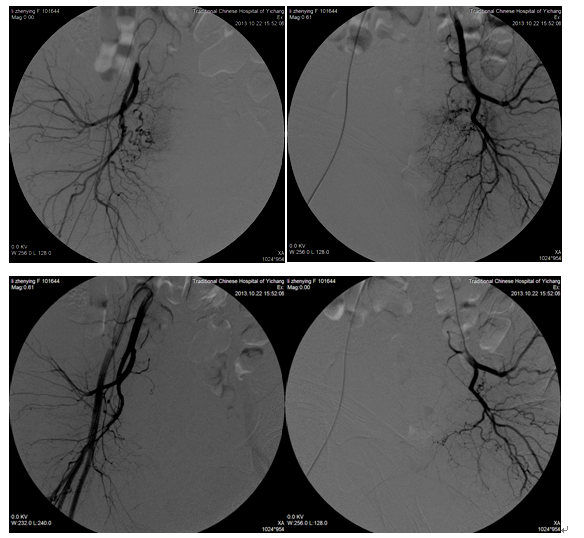

女、宫颈癌盆腔广泛转移腹部剧烈疼痛,在我院采用中药制剂结合介入盆腔内肿瘤血管灌注术后,肿瘤血管闭塞,疼痛明显减轻,睡眠改善。